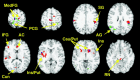

We examined brain-behavior correlations in 12 children (age range 9.3 to 11.7 years) during a selective attention task that required the visual search of a conjunction of features and during a response inhibition task that required the inhibition of a pre-potent response during "no-go" blocks. We found that the association between performance in these tasks and brain activation as measured by functional magnetic resonance imaging (fMRI) depended on the neurocognitive network. Specifically, better performance during the no-go task was associated with greater activation in the response inhibition network including the prefrontal cortex and basal ganglia. In contrast, better performance during the visual search task was associated with less activation in the selective attention network including superior parietal lobule and lateral premotor cortex. These results show that the relation of performance to the magnitude of neural activation is complex and may display differential relationships based on the cognitive domain, anatomical region, and perhaps also developmental stage.